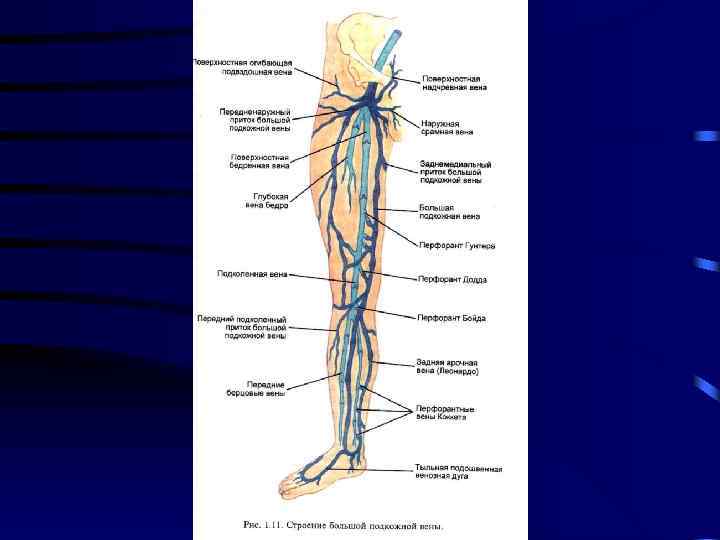

• Тромбофлебиты на нижних конечностях у 90 -95% больных • Тромбофлебиты глубоких вен у 80% • Тромбофлебиты поверхностных вен у 20%

Острый тромбофлебит – острое воспаление венозной стенки с образованием тромба в просвете сосуда с нарушением оттока крови по вене. • По месту локализации различают: • • Тромбофлебит подкожных вен Тромбофлебит глубоких вен Тромбофлебит подвздошных вен Тромбофлебит подключичной вены – синдром Педжета-Шреттера

Хронические заболевания вен: • Варикозная болезнь: – Страдают женщины 5: 1 – В России 38 -40 млн. людей с венозной недостаточностью